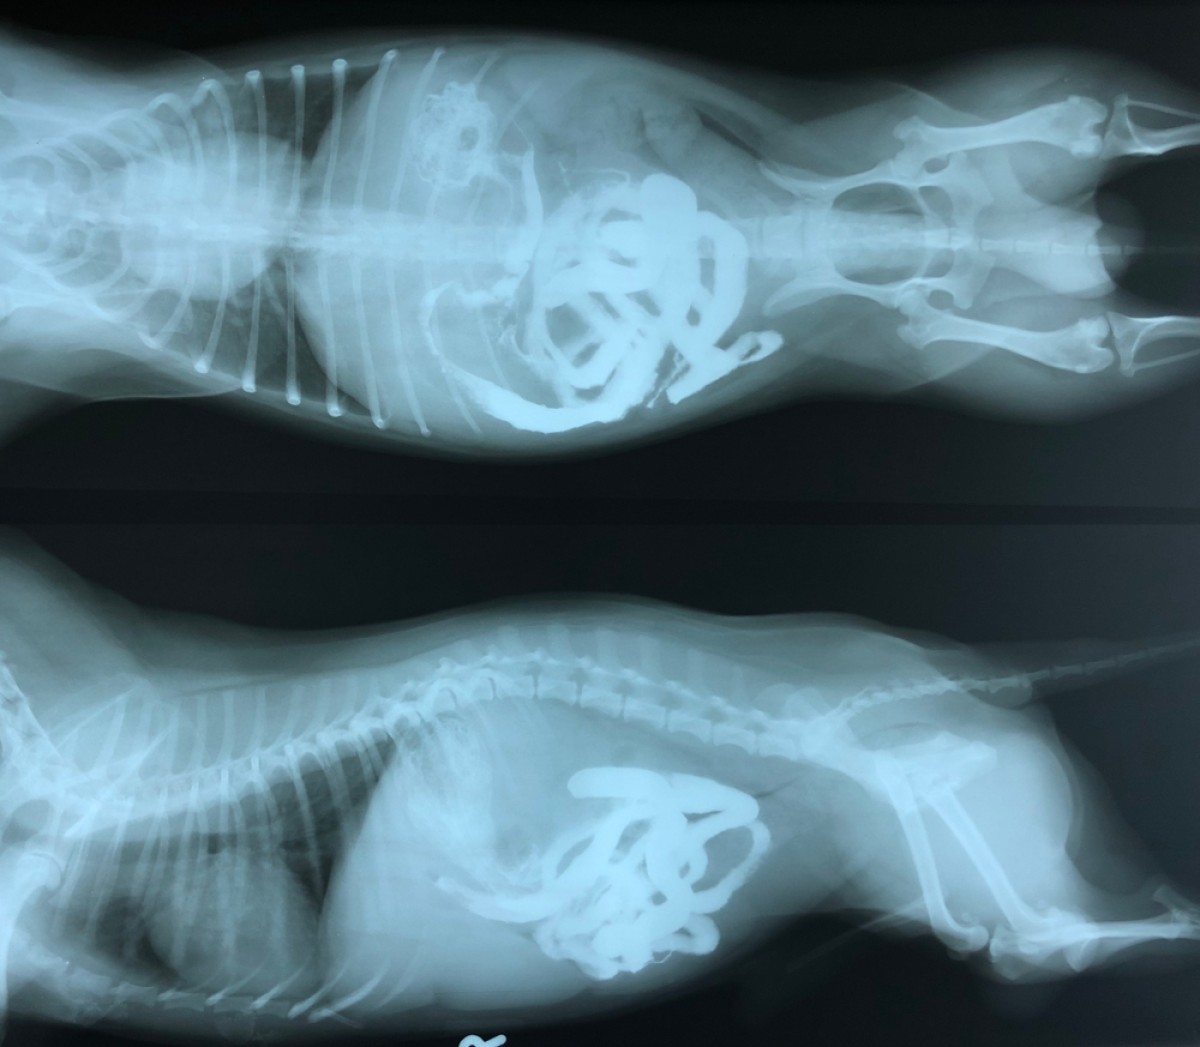

Stabilisation des fractures du sacrum chez le chien et le chat